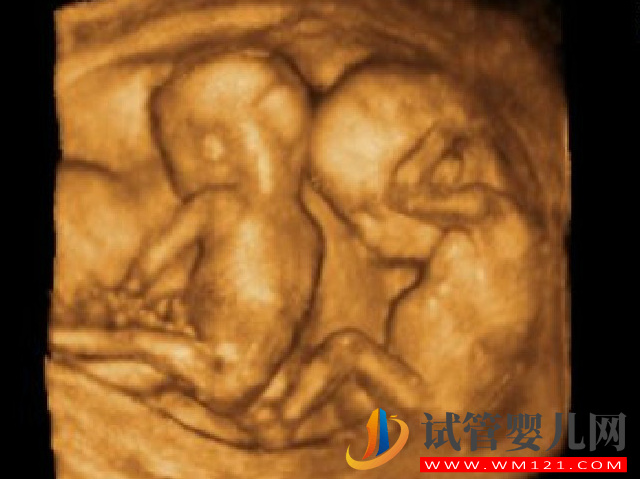

妊娠期血糖偏高會(huì)不會(huì)造成雙胎一起胎停?

妊娠期血糖高是會(huì)導(dǎo)致雙胎一起出現(xiàn)胎停的可能。妊娠期血糖高可能是因?yàn)樽陨硖谴x異常導(dǎo)致的,但也有可能是孕期飲食攝入不合理導(dǎo)致的一過性血糖高。如果懷孕期間血糖過高,不僅對(duì)孕媽自身健康有影響,還會(huì)直接影響到胎兒的正常發(fā)育,導(dǎo)致胎兒發(fā)育緩慢、滯后等問題,如果嚴(yán)重的話是會(huì)出現(xiàn)胎停的。尤其是懷雙胎的情況,就更容易引發(fā)妊娠血糖高的情況,也很容易導(dǎo)致胎停的情況發(fā)生。

一般懷有雙胎的時(shí)候,身體負(fù)擔(dān)較重,是比較辛苦的,特別是對(duì)營(yíng)養(yǎng)的需求量也比較大。是很容易導(dǎo)致雙胎一起出現(xiàn)胎停的情況,所以孕期需多個(gè)方面有效注意,才能使身體更好地適應(yīng)。其實(shí)導(dǎo)致雙胎一起停的因素還是比較多的。